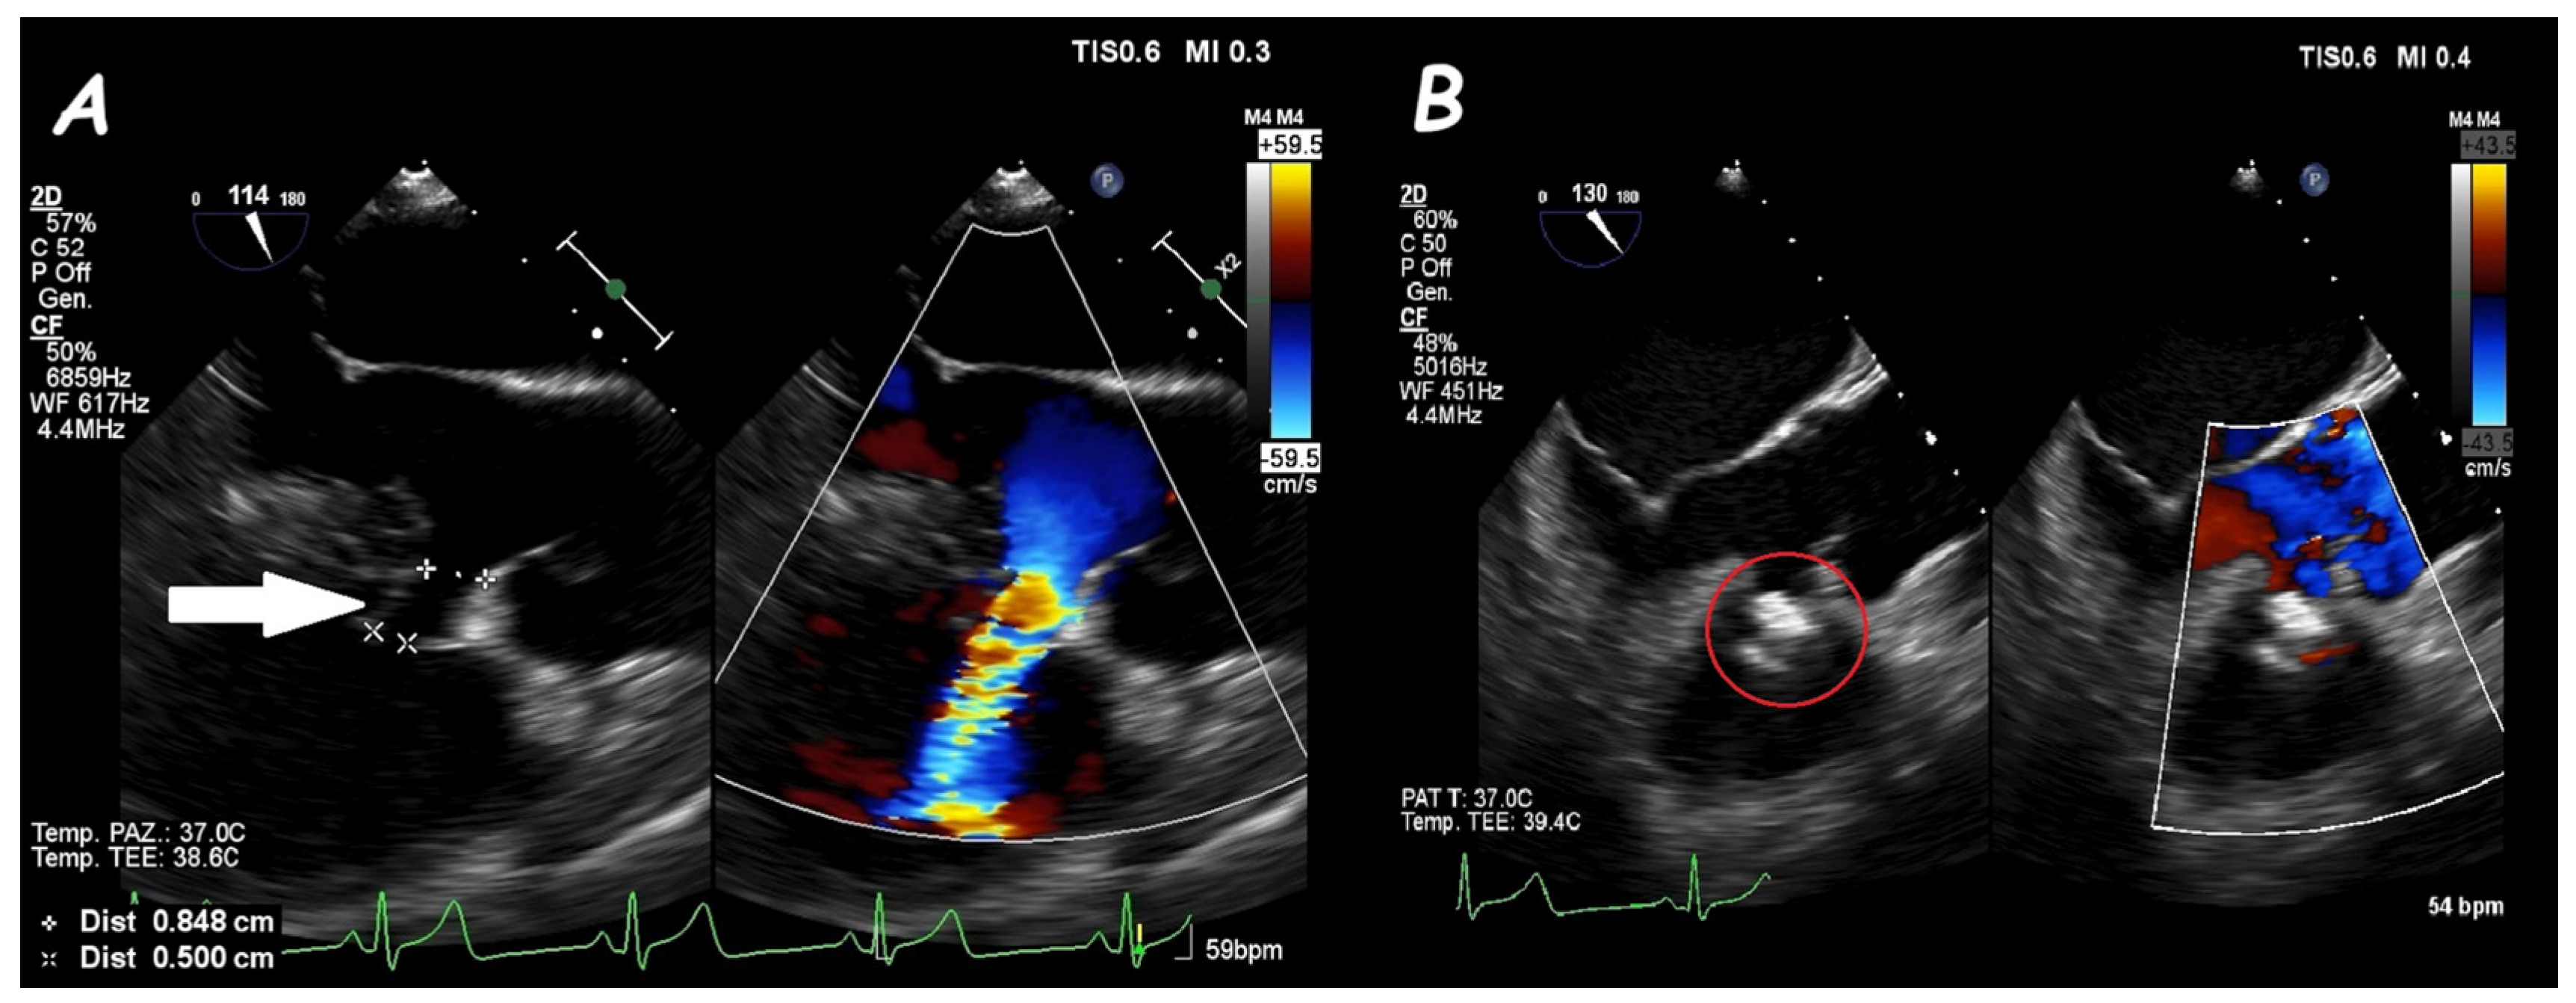

6. Ruptured Sinus of Valsalva Closure